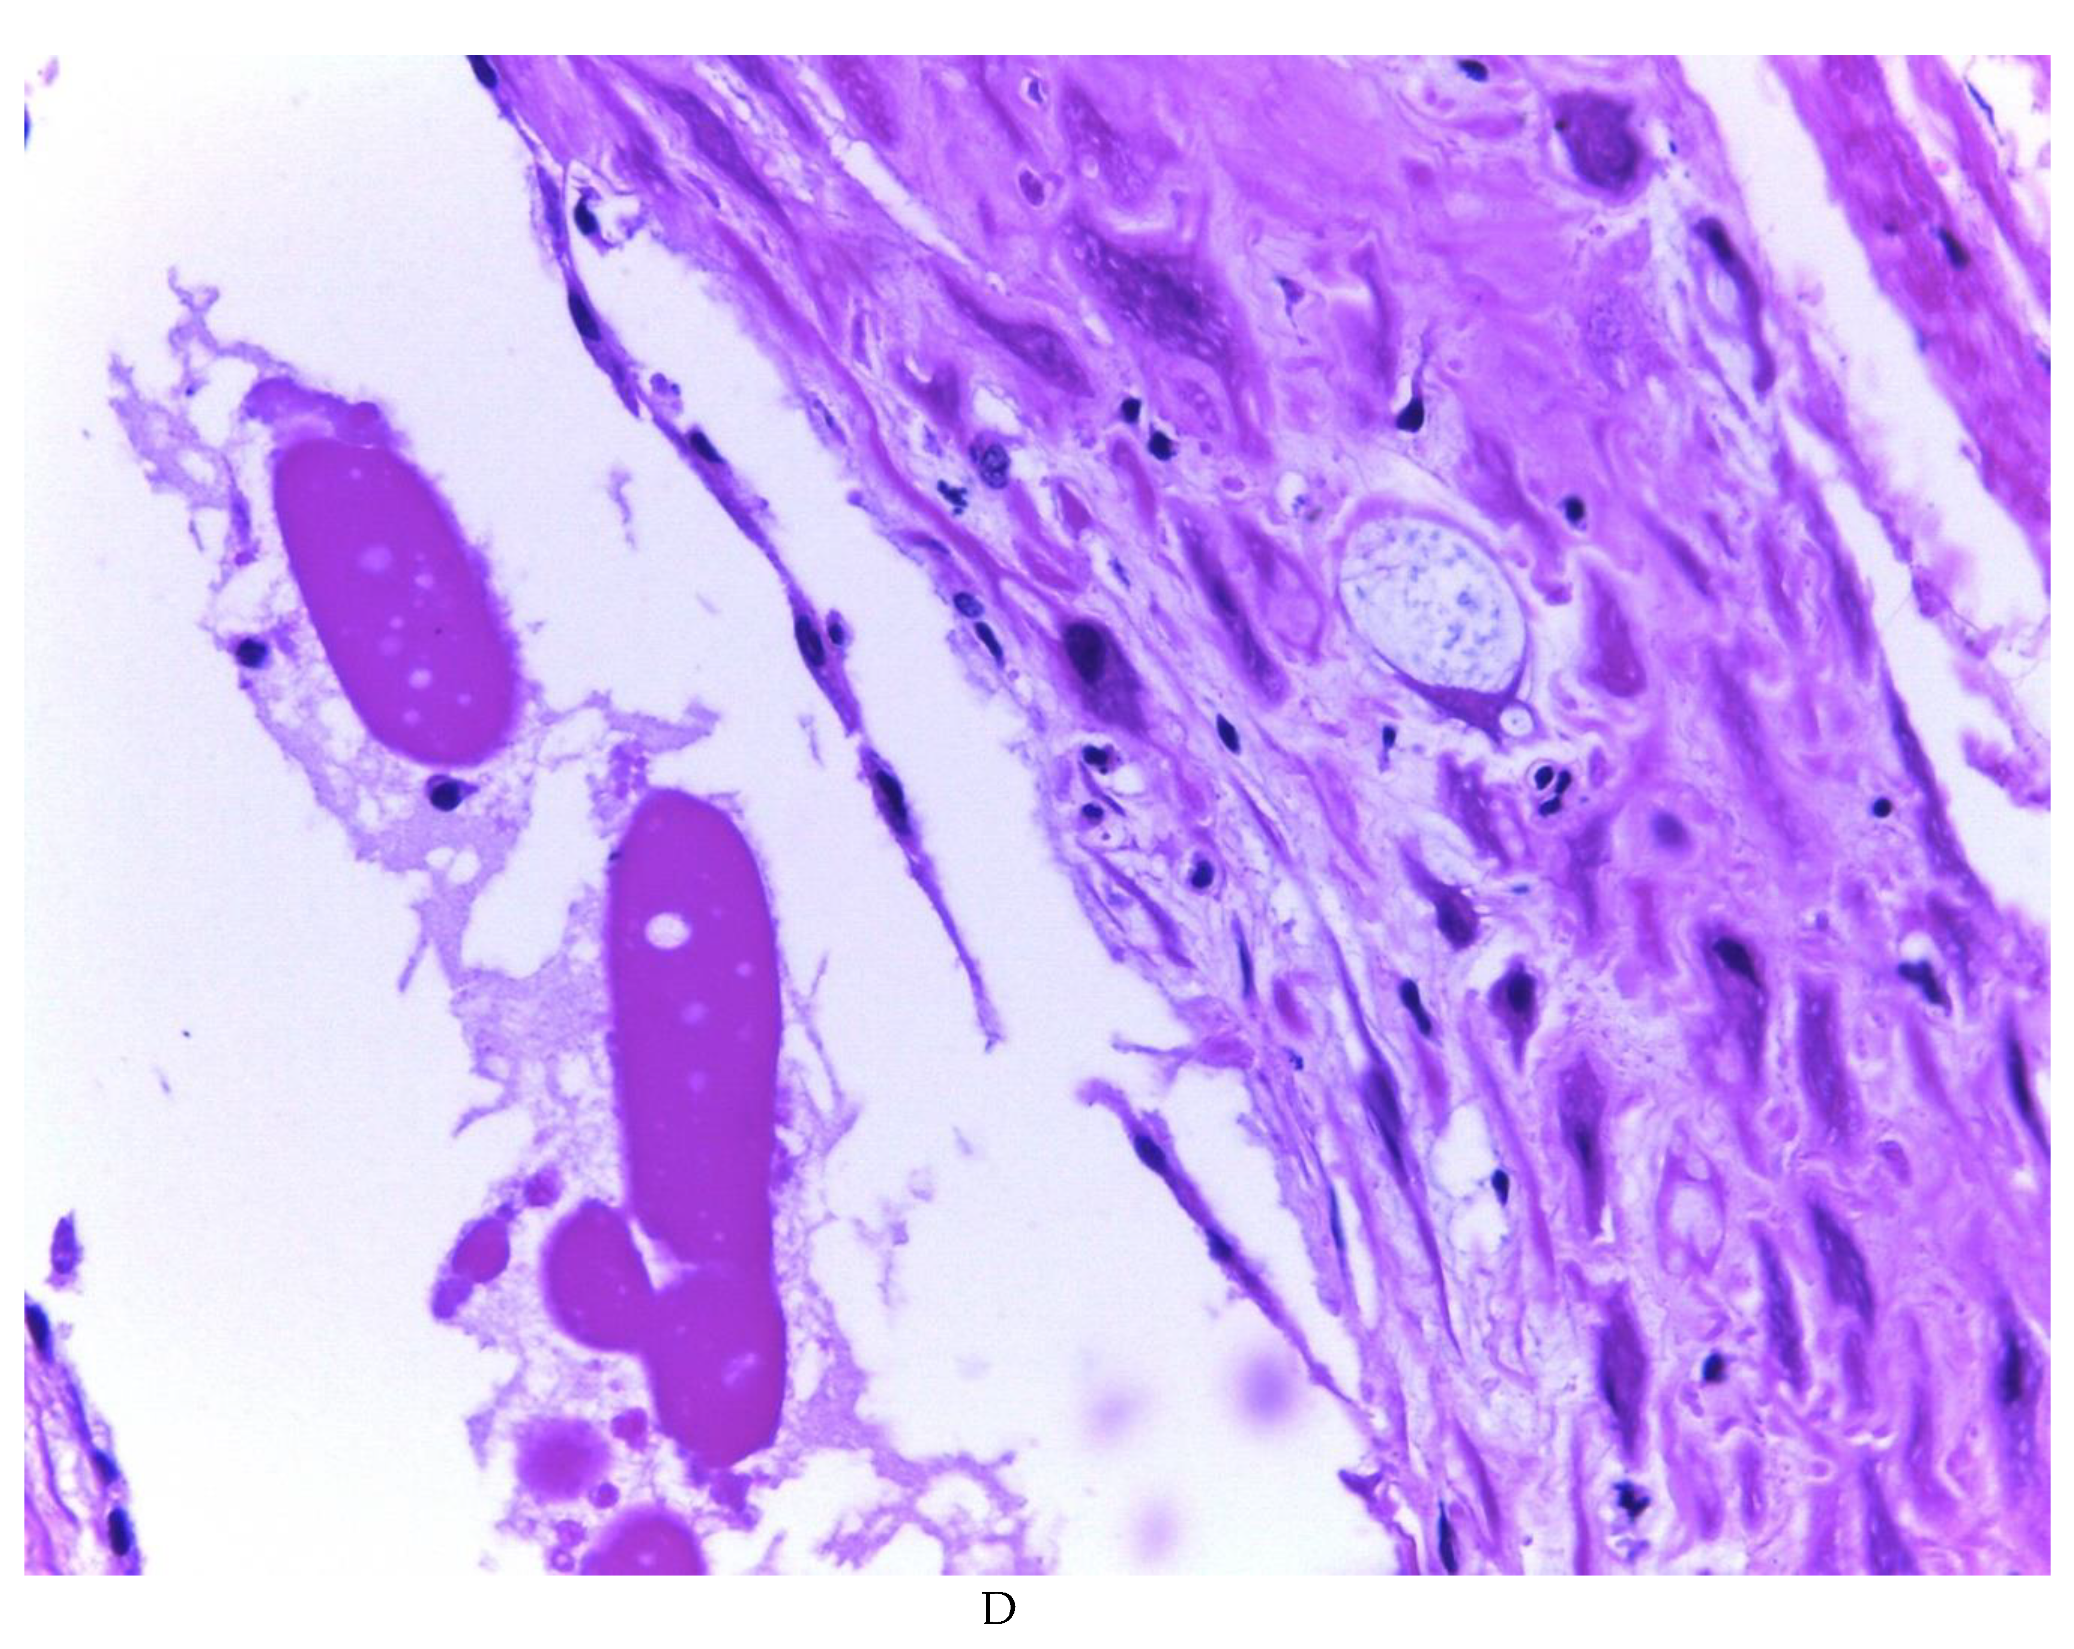

776 cases of endometriosis were collected between the two institutions participating in the study, in different anatomical sites (Table 1, Figure 1), in which 54 of them presented a myxoid stroma greater than 50% with respect to the cellularity of the samples. and that represent 6.95% of the total endometriosis examined with the following locations: omentum (4/20), ileum (2/4), ovary (14/216), parametria (2/9), soft tissues (28/235), salpingus (3/77), bladder (1/4). The clinical records of these patients were consulted and the common denominator was that the women were in the surgical (41/57) or physiological (7/39) puerperium in a period of time from 24 hours postpartum to six months after said event. Macroscopically, two different lesions were observed: the first one, which is the most frequent, presents as a non-encapsulated lesion with pushing edges of a fibromyxoid appearance; the second and less frequent, a well-defined lesion, partially or totally encapsulated, the cut surface is shiny, gelatinous in appearance, multilobed, light brown to brown in color with focal areas of recent and old hemorrhage, these lobes are separated by fibrous septa (Figure 2). Histologically, it was found in all the samples evaluated at least 50% of myxoid stroma with some fine connective tissue septa with proliferation of stromal cells (Figure 3A), which present four variants in their shape: (1) Epithelioid stromal cells of wide eosinophilic cytoplasm with round nucleus with small nucleolus (Figure 3B), (2) Pseudolipoblast-type stromal cells with moderate cytoplasm, multivacuolated in their cytoplasm that can present eosinophils or be clear cytoplasm, with central nuclei of granular chromatin (Figure 3C), (3) “pseudosignet ring” stromal cells with nucleus and cytoplasm rejected to the periphery giving the aforementioned appearance (Figure 3D) and (4) immersed spindle cells with small nucleus and barely visible nucleolus (Figure 3E); Among these cells, the epithelial component is observed, which is forming tubules that vary in diameter, ranging from small tubules and large cystic dilations of the gland that presents a layer of low cubic to cylindrical epithelium, generally with an atrophic appearance (Figure 3F). Hyaline globules were found in the glandular lumens (Figure 3G). The extracellular matrix showed a composition by glusocaminoglycans evidenced in 100% of the cases by staining present for AA (Figure 4A–C), but without staining for PAS; however, the latter stained on proteinaceous globular material in the lumen of the endometrial glands (Figure 4D). Immunohistochemistry for CD10 was positive in 100% of the stromal cells with a mild to moderate reaction in the cytoplasm and membrane with a decidual appearance (Figure 5A,B). The ER and PR showed nuclear expression in 100% of the cases, with greater intensity in the ER (Figure 5C) than in the RP (Figure 5D); both hormone receptors were expressed on endometrial epithelial cells as well as on stromal cells. The cases of myxoid endometriosis examined did not present cytological atypia suggesting any precursor lesion of epithelial or stromal origin.

Figure 3. Histologic features of myxoid endometriosis: A) Myxoid stroma in 50% or more of the tissue, with proliferation of stromal cells. Identified stromal cell variants: B) epithelioid cells, C) lipoblast-like cells, D) signet-ring-like cells, E) spindle cells. F, G, H) Epithelial component formed by glands of variable size, with simple cuboidal to columnar epithelium with a non-atypical atrophic appearance, occasionally accompanied by luminal hyaline globules.